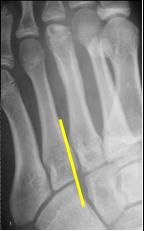

The normal midfoot